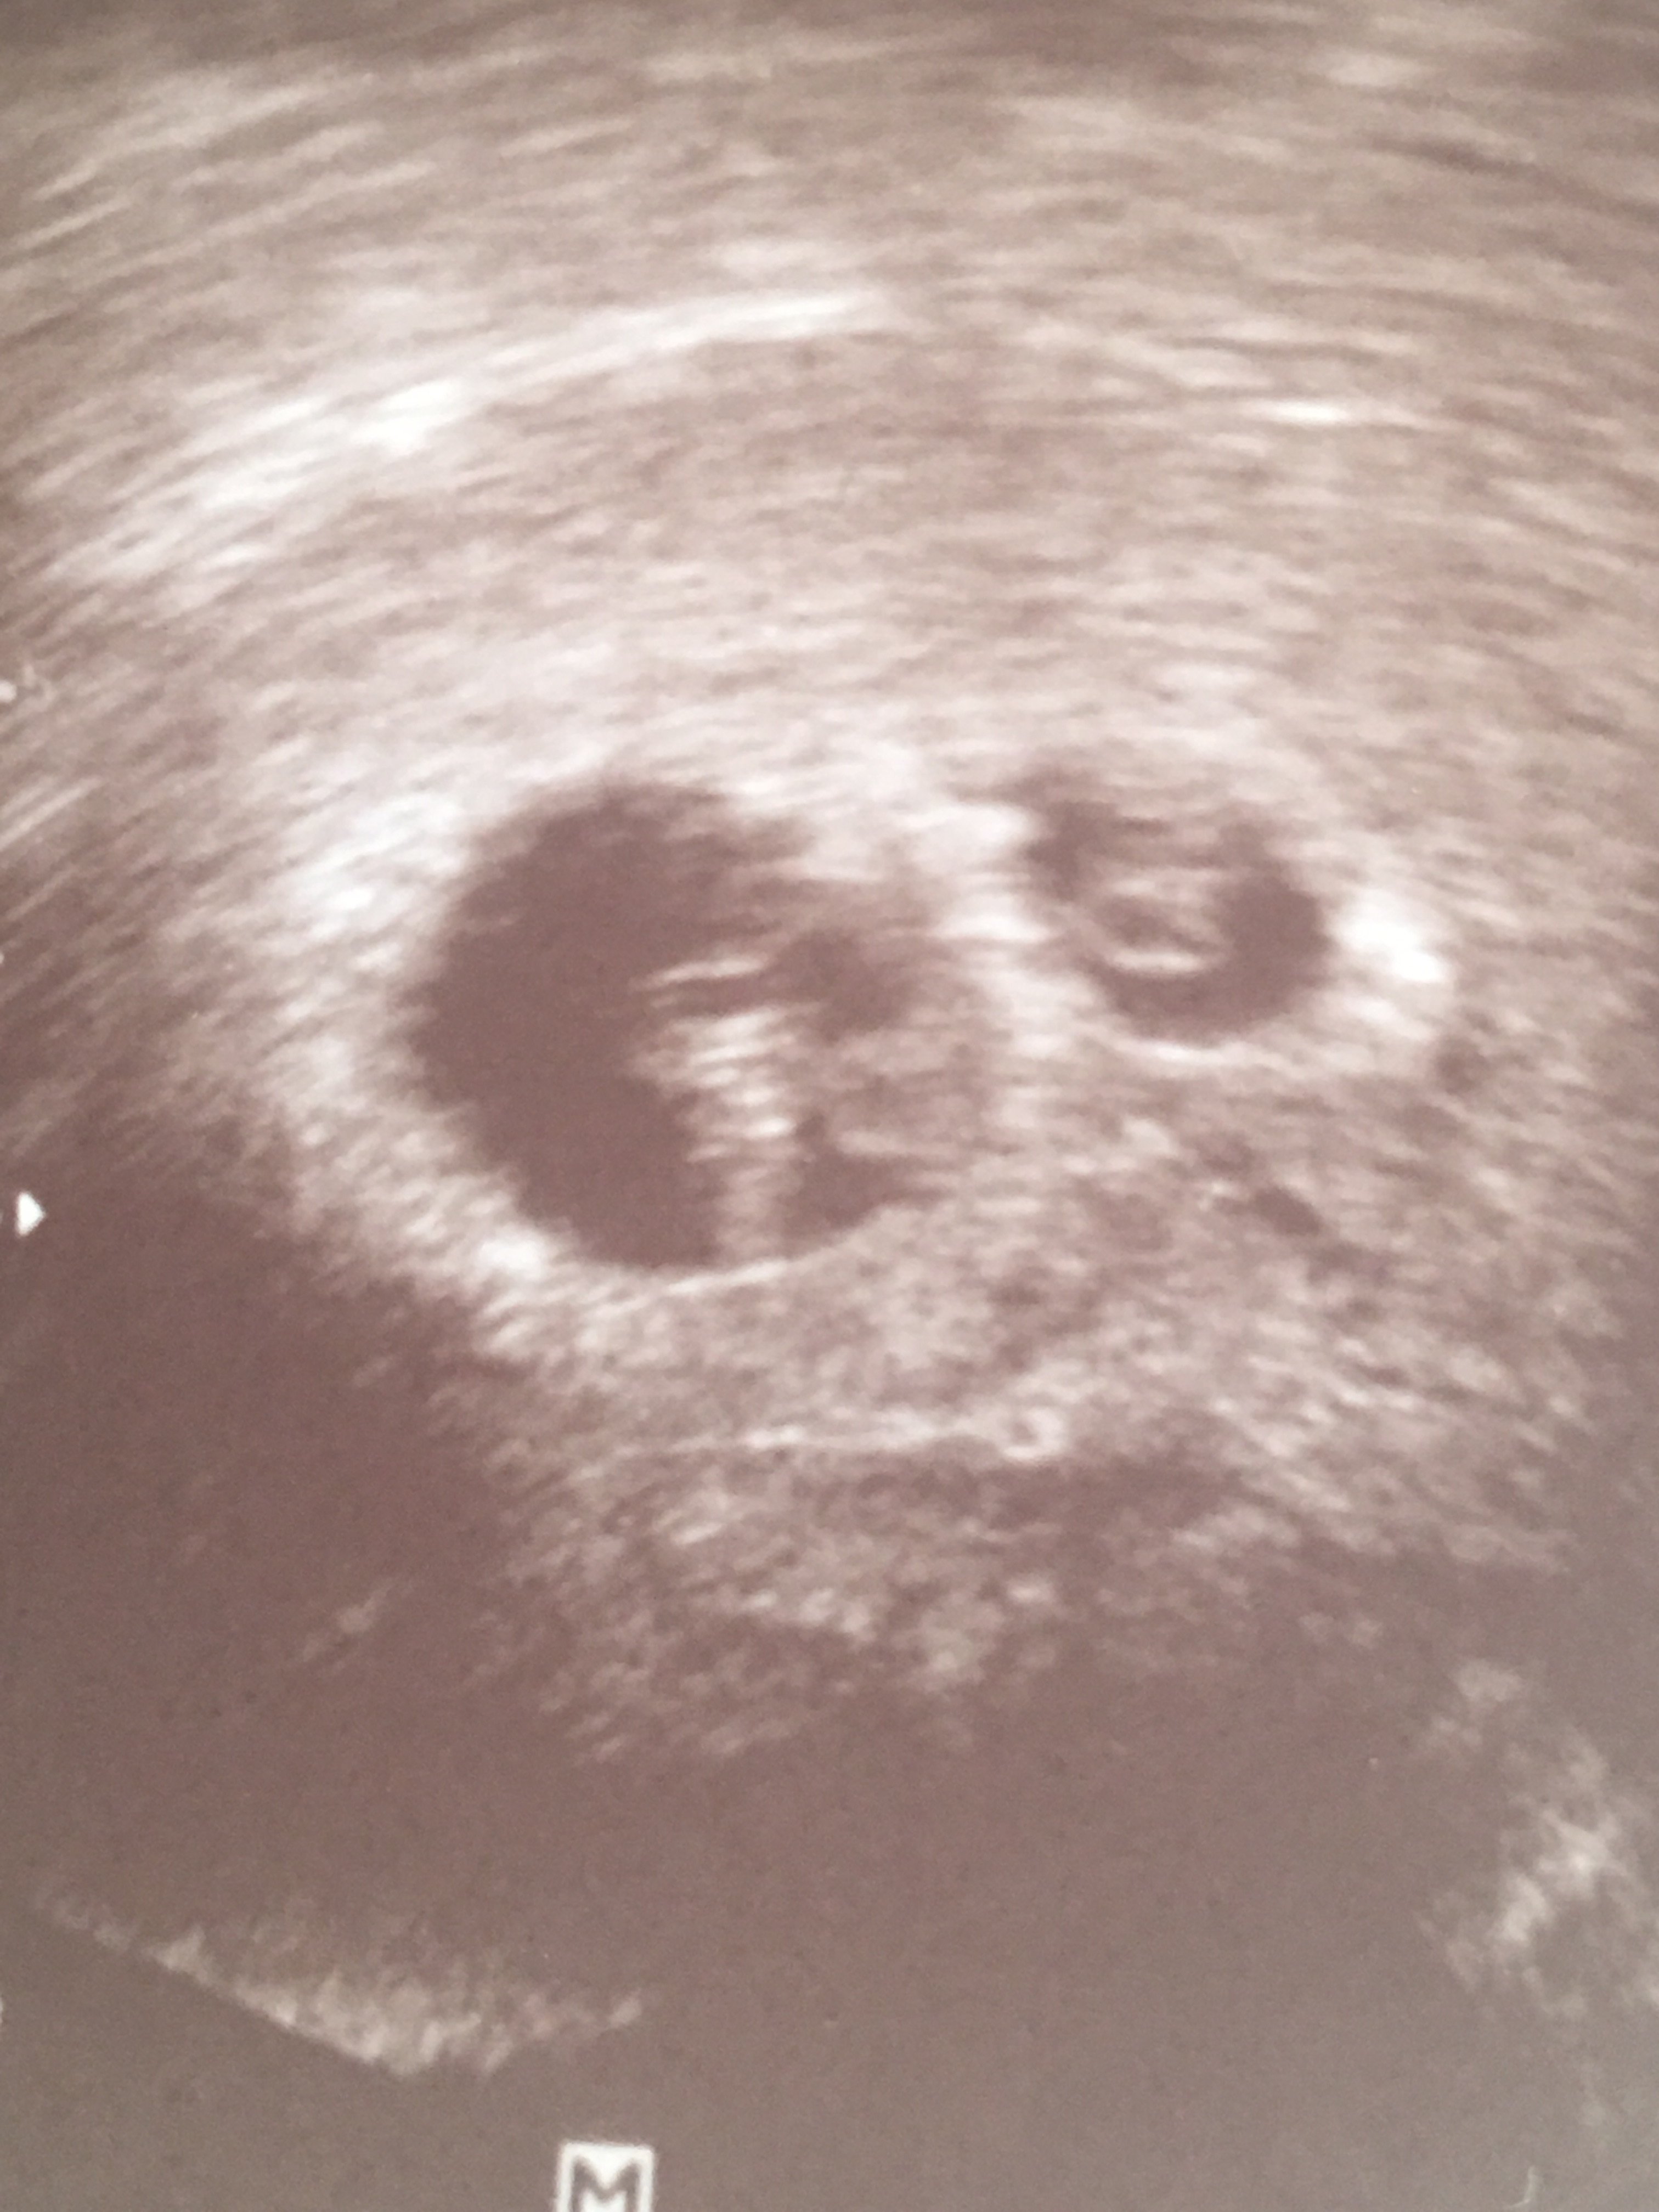

O mój Boże! Gratulacje! Dawno tu nie zaglądałam i takie piękne widoki!!! [emoji7][emoji7][emoji7][emoji7][emoji7][emoji7][emoji7]Dwa bijace[emoji173]️[emoji173]️Zobacz załącznik 906756